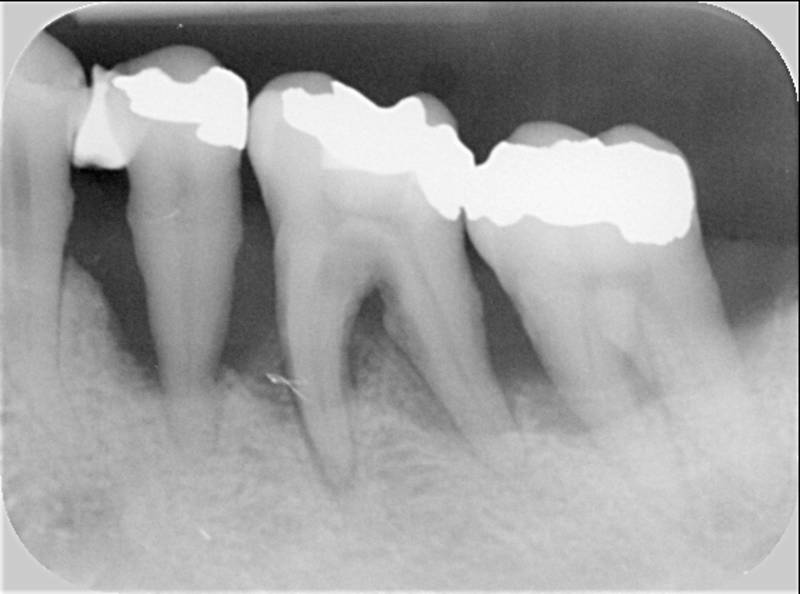

Qeyri-cərrahi parodontoloji müalicədən sonra bəzi hallarda, bu və ya digər bölgədə dərin parodontal ciblər (diş əti və sümük cibi) qalmaqda davam edir. Bu hallarda çox zaman müalicə cərrahi metodların tətbiqi ilə davam etdirilir. Bu zaman əsas məqsəd mövcud parodontal cibin bu və ya digər metodlarda aradan qaldırılmasını təmin etməkdir.

Çünki bu ciblər çox zaman pasiyent tərəfindən yetərincə təmizlənə bilmir. Bu isə həmin bölgəyə tədricən ərp və dolayısı ilə də bakteriya koloniyalarının toplanmasına səbəb olur. Bu proses yenidən yerli iltihabın ortaya çıxmasına səbəb olur. Tətbiq edilən cərrahi metodlar əsasən cibin yerləşdiyi diş bölgəsi, cibin eni, dərinliyi, konfiqurasiyası və s. xüsusiyyətlərə görə müəyyənləşdirilir. Bu zaman məqsəd mümkün olduqda həmin bölgədə bərpa prosedurunu həyata keçirmək, mümkün olmadıqda isə rezektiv müalicənin tətbiqi ilə həmin bölgəyə ərp toplanma ehtimalını azaltmaq və gigiyenik prosedurların icrasını pasiyent üçün rahatlaşdırmaqdır.